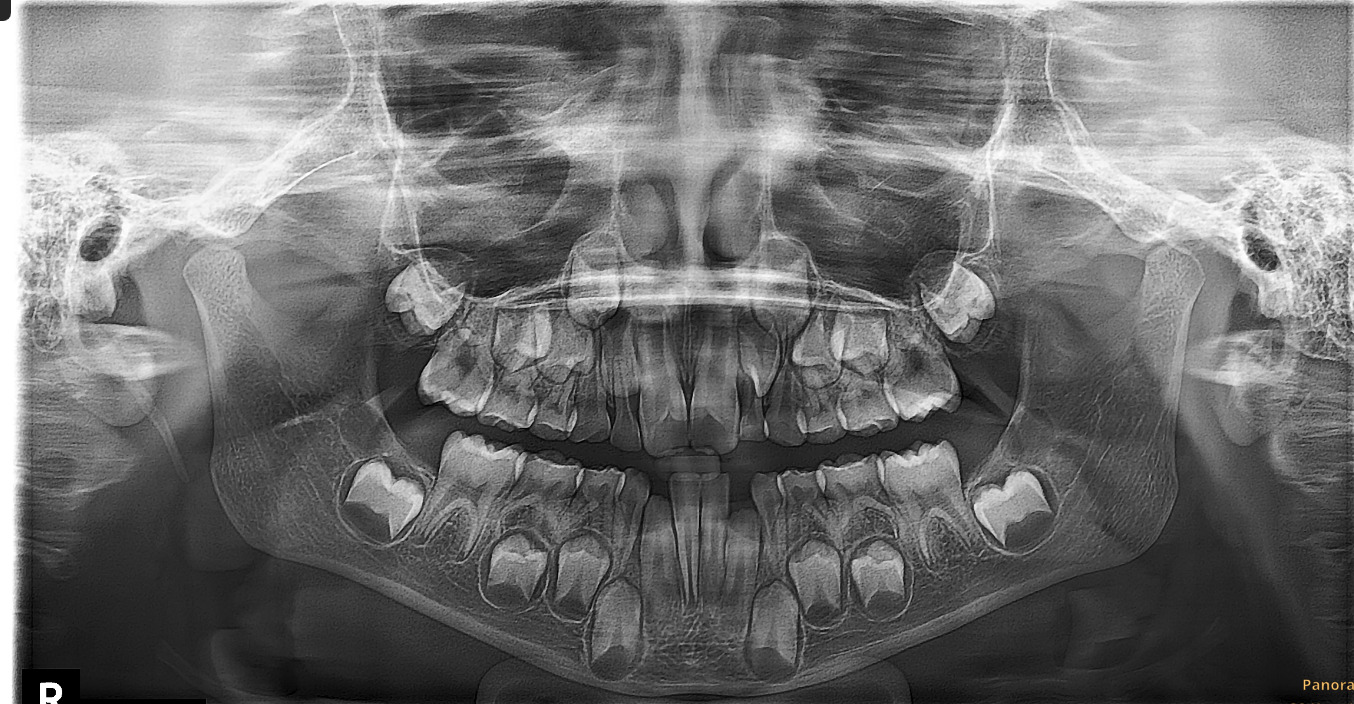

Фотографии ортопантомограмм и работ Родена